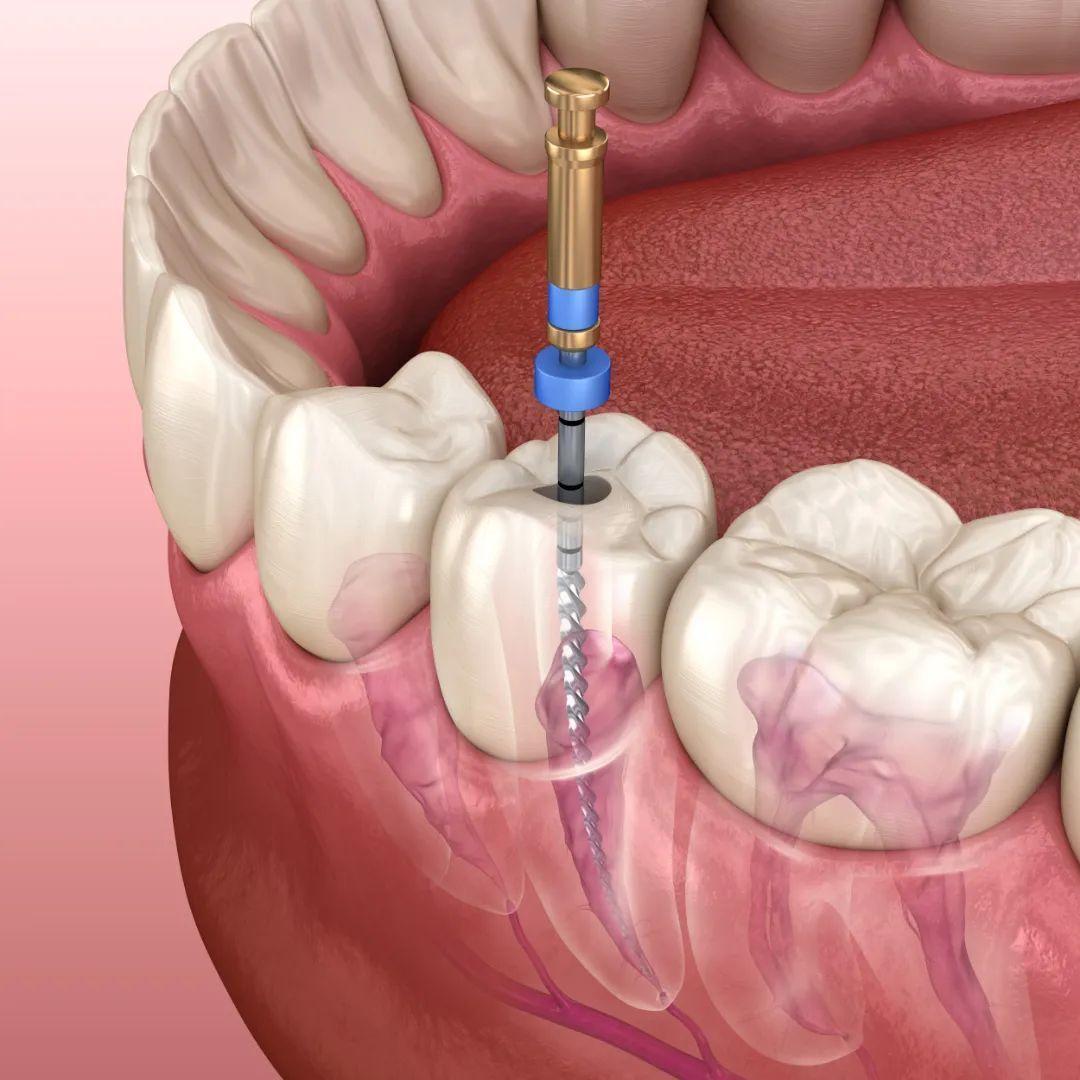

抽牙髓

抽出你的牙神经,根管治疗时,你要懂的一些事-王俞方-爱问医生

图片尺寸720x480